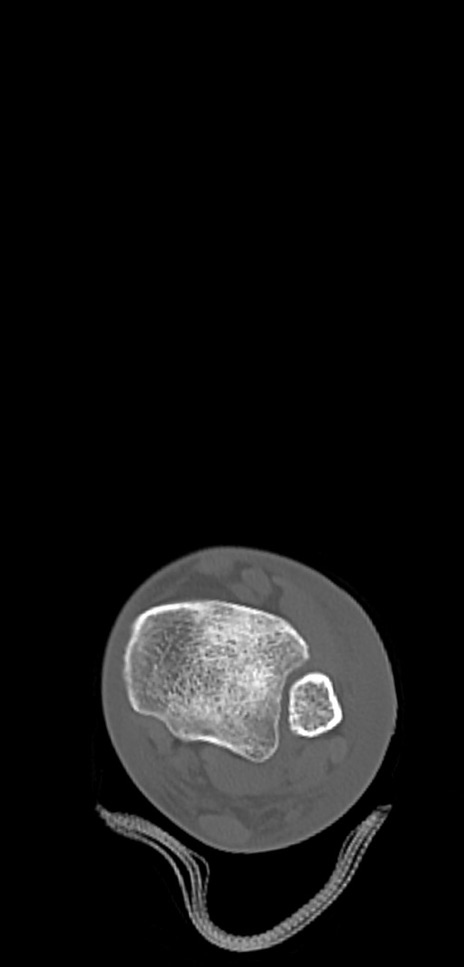

左足関節CT

冠状断像